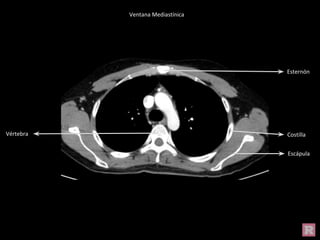

Ventana Mediastínica

Esternón

Escápula

V.

braquiocefálica

izq

V. braquiocefálica

der

A. carótida izq

A. Subclavia izq

A. Braquiocefálica

A. Subclavia der

Lóbulo superior

Esófago